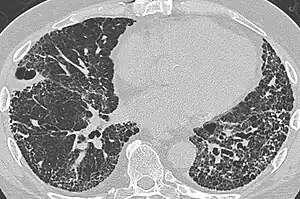

CT scan in a patient with usual interstitial pneumonia, showing interstitial thickening, architectural distortion, honeycombing and bronchiectasis.

Honeycombing or "honeycomb lung" is the radiological appearance seen with widespread pulmonary fibrosis[1] and is defined by the presence of small cystic spaces with irregularly thickened walls composed of fibrous tissue. Dilated and thickened terminal and respiratory bronchioles produce cystic airspaces, giving honeycomb appearance on chest x-ray. Honeycomb cysts often predominate in the peripheral and pleural/subpleural lung regions regardless of their cause.

Subpleural honeycomb cysts typically occur in several contiguous layers. This finding can allow honeycombing to be distinguished from paraseptal emphysema in which subpleural cysts usually occur in a single layer.